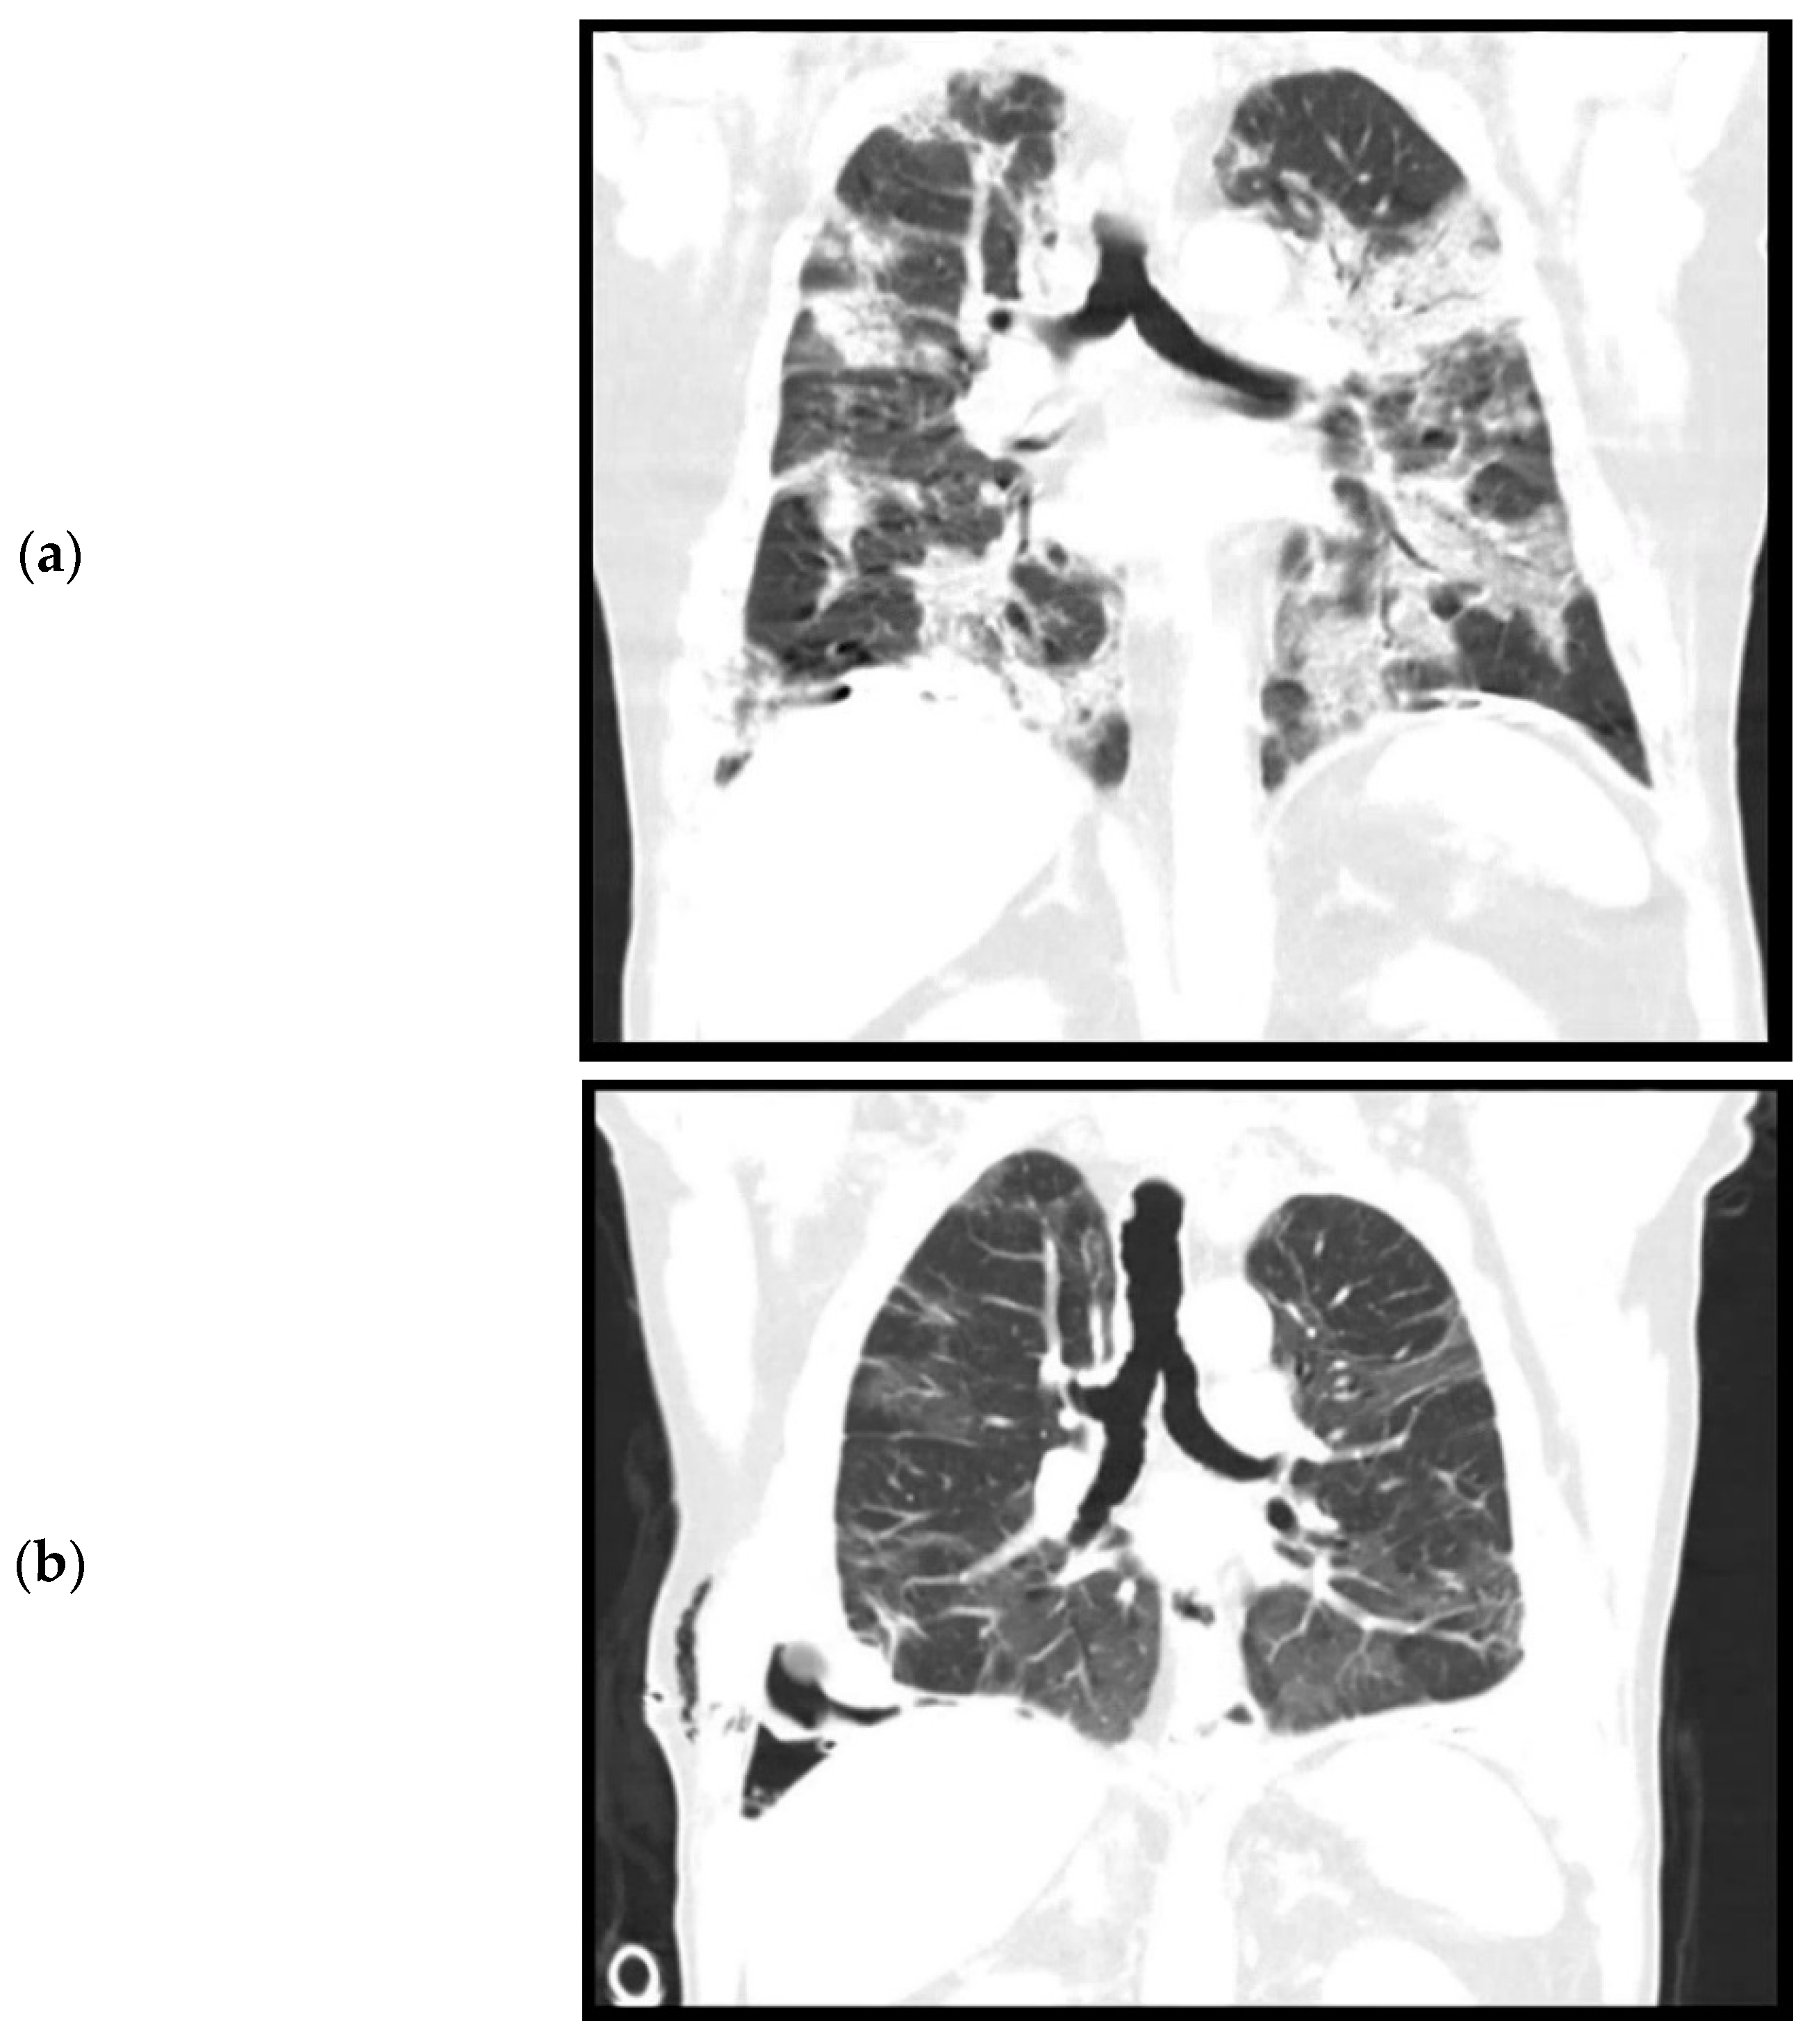

Figure 1.

Computed tomography, coronal plane. (a). April 2020. Level of trachea bifurcation. Bilateral consolidations and ground glass opacities during active SARS-CoV-2 infection. (b). September 2020. Level of trachea bifurcation. Bilateral residual ground glass opacities. (c). September 2020. Level of thoracic vertebrae. Right sided loculated pleural effusion, pleural empyema, and trapped lung.

During admission, the patient did not have a fever. Oxygen saturation was 97% with 6 L oxygen. Laboratory results showed a white count of 16.6 × 109/L (reference: 4.0–10.0 × 109/L) and a C reactive protein (CRP) of 139 (reference < 5.0). Chest X-ray and chest CT performed on the day of admission showed bilateral consolidations and ground glass opacities without pleural effusion, suspicious for a COVID-19 infection (Figure 1a). Furthermore, pleural plaques were present on the right and left hemidiaphragm without evidence of round atelectasis or focal ischemia of the lung parenchyma. Multiple Polymerase Chain Reaction (PCR) for SARS-CoV-2 from nasopharyngeal swabs were negative, but after a few days a SARS-CoV-2 rectal swab was positive. This test was never repeated. The patient was admitted for oxygen support through a nasal cannula and cefuroxime and azithromycin were administered to prevent a bacterial superinfection. Furthermore, prophylactic low molecular weight heparin (nadroparine, 2850IE once daily) was started. The patient did not require mechanical ventilation. On the eleventh day of admission, a CT angiography of the chest was performed because of ongoing oxygen support. This showed a decrease in consolidations, but new bilateral segmental pulmonary embolisms, for which dabigatran was initiated. No coagulation parameters were tested during the admission. The patient could be weaned off oxygen support and after two weeks of admission, was discharged to a nursing home for further recovery. From there, eventually patient was discharged home in good condition.

The patient was re-admitted for observation. Laboratory results showed a white count of 10.7 × 109/L and a CRP of 79. A culture of the pleural fluid was negative for bacteria. A chest CT performed after drainage showed bilateral residual ground glass opacities after the initial COVID-19 infection (Figure 1b) and a right-sided loculated pleural effusion (Figure 1c), suspicious for a thoracic empyema. The patient was referred to our hospital, a tertiary care center for thoracic surgery, for pleural decortication.